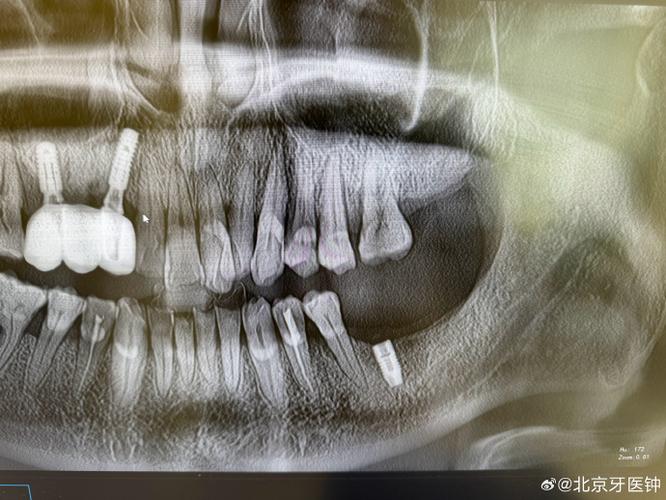

(图片来源网络,侵删)